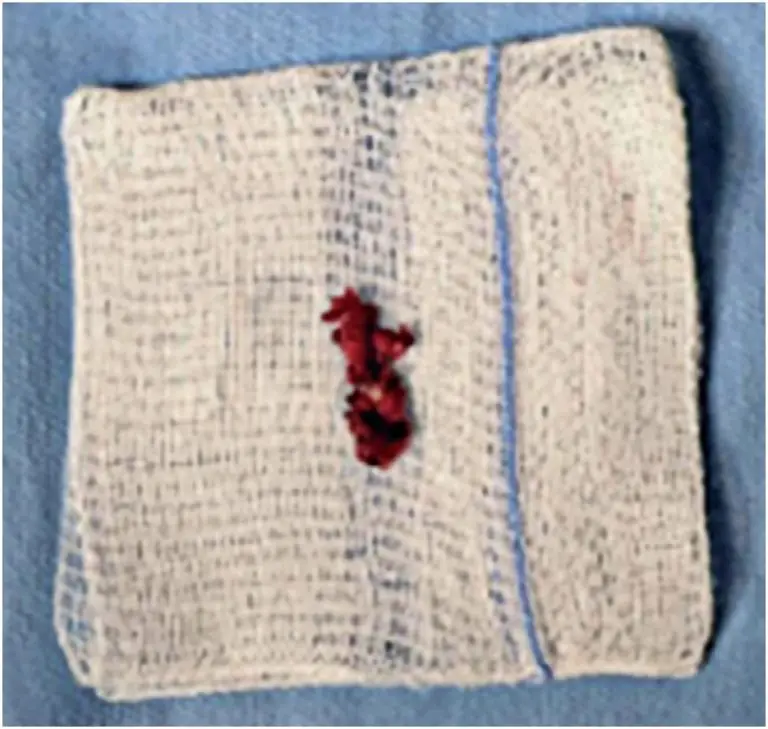

Perineural hematoma following lumbar injection presenting as a neurosurgical emergency

DOI: 10.31744/einstein_journal/2025RC1483

ABSTRACT Lower back pain and sciatica account for approximately 40% of work-related absences, with management options ranging from conservative measures, such as rest and analgesia, to surgical intervention. Lumbar epidural steroid injections and facet joint blocks are frequently used for both diagnostic and therapeutic purposes. While most complications are minor (2.4%-9.6%), severe events, including infection, hematoma formation, and spinal cord infarction, have been reported. This case presents a perineural hematoma manifesting as acute radiculopathy, necessitating urgent surgical decompression. The patient […]

Palavras-chave: Descompression, surgical; Hematoma; Injections; Dor lombar; Imagem por ressonância magnética; Perineural; Radiculopathy; Sciatica